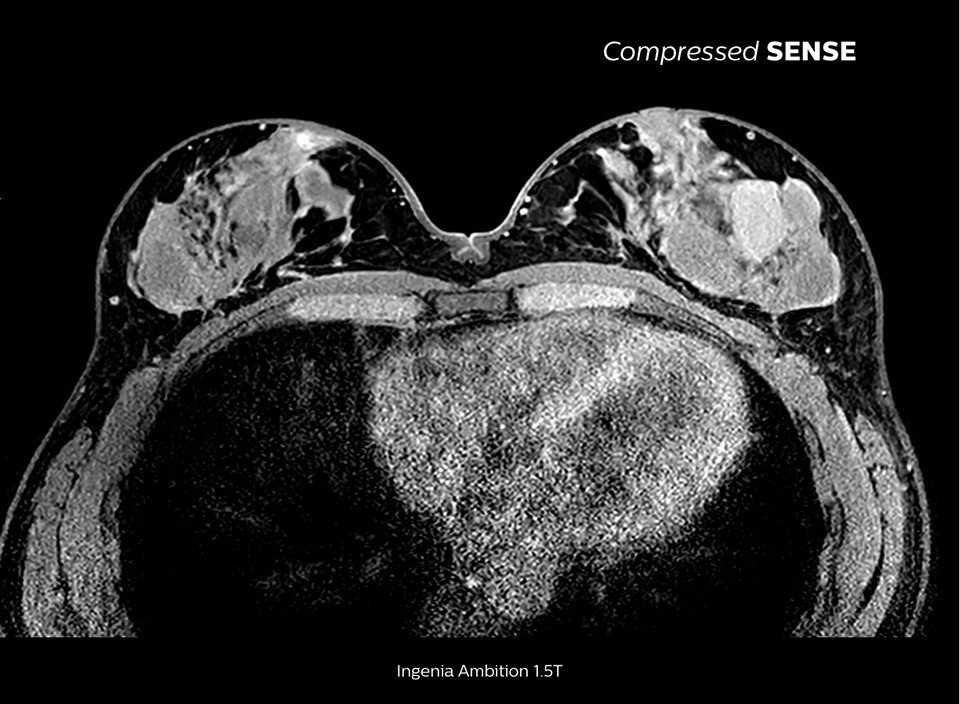

Faster scanning, with

virtually equal image quality

Up to 50% faster 3D sequences, with virtually equal image quality1

Compare the time savings of an MRI scan performed with Compressed SENSE MRI software versus a conventional scanning technique